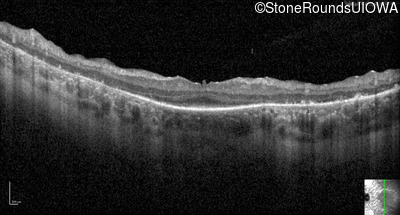

Optical Coherence Tomography - Right - 20/63

Exemplar / OCT Stack